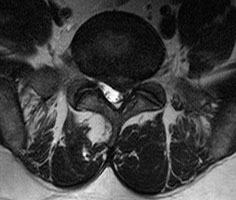

Die Magnetresonanztomografie mit Kontrastmittelgabe und STIR-Sequenz ist die Standardbildgebung zum Nachweis auch schon von frühen Veränderungen, noch bevor Knochendestruktionen auftreten.

.